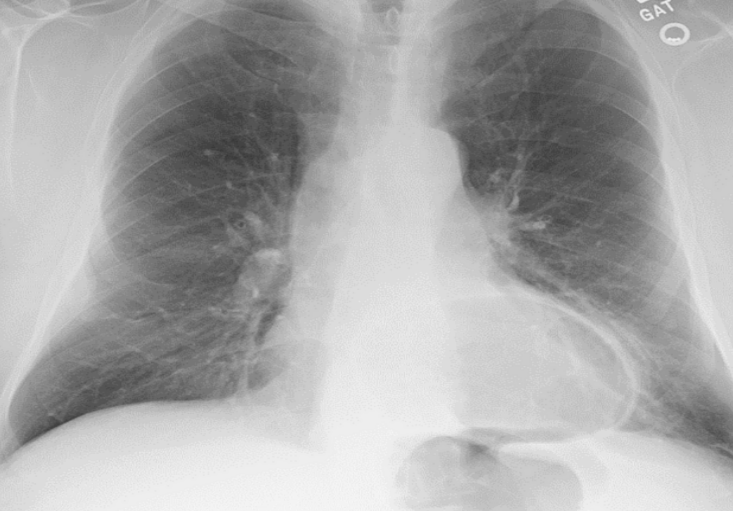

AP chest X-ray (critically ill patient and intubated)

tracheal intubation (above the carnia. if lower it will inter right main stem bronchous→leads ti left lung collaps)

NG tube

Central line (into SVC)

left main stem bronchous showing radio-opacity and patent bronchioles→Air broncho-grams (if localised→indicates infectious process)

Bilateral diffuse lung opacities on both lung fields (slightly more on left side)

Ddx: ARDs, decomensated heart failure, aspiration

Air bronchograms